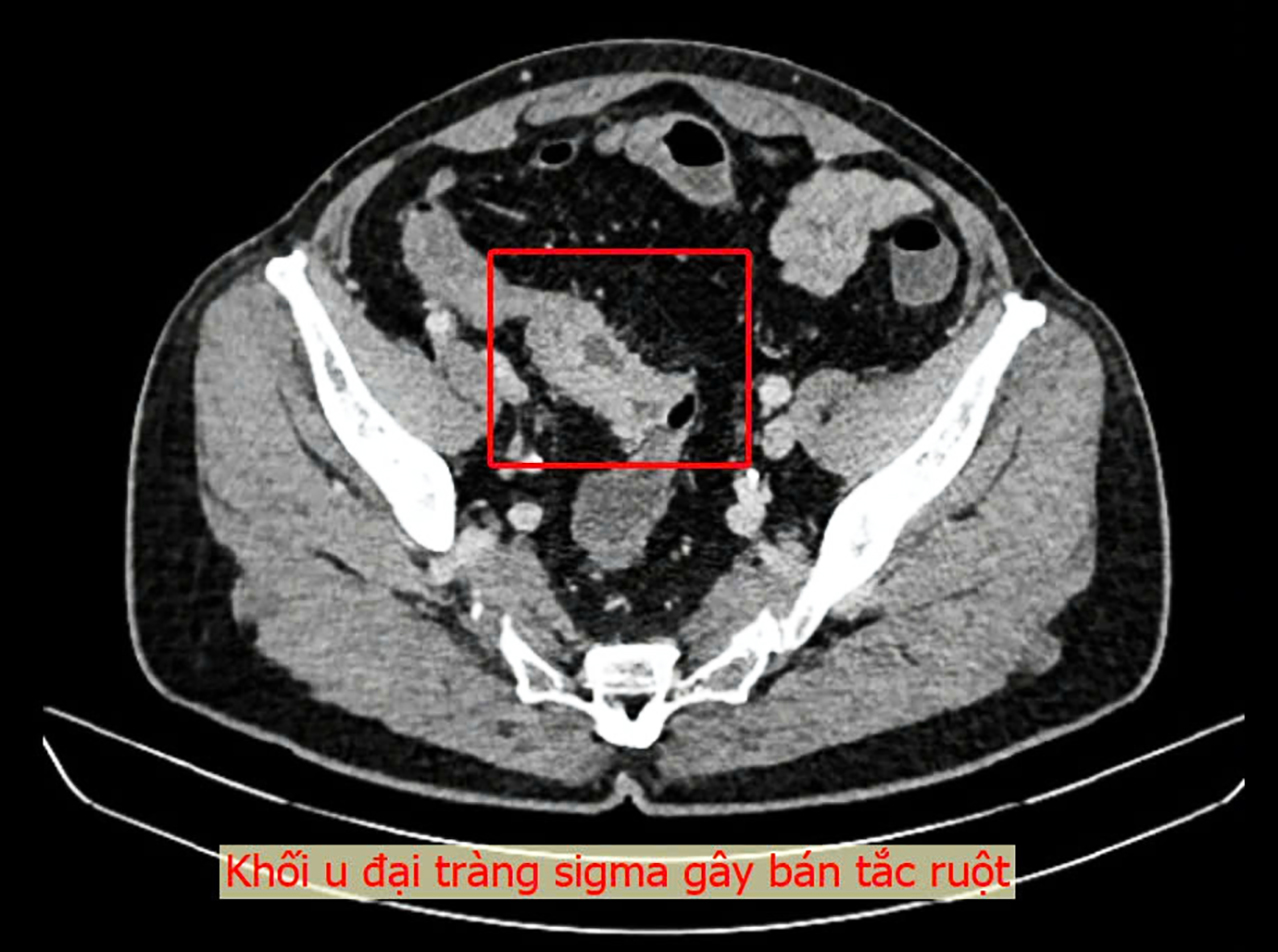

Trong thời gian về Việt Nam, bệnh nhân đã đến khám tại Bệnh viện Đa khoa Thủ Đức. Qua nội soi đại tràng, các bác sĩ phát hiện một khối u lớn tại vị trí sigma-trực tràng, chiếm trọn lòng trực tràng, với đặc điểm mô bở và dễ chảy máu. Sau khi đánh giá toàn diện và xét nghiệm cần thiết, ekip bác sĩ xác định đây là khối u ác tính và cần phẫu thuật gấp.

Ca phẫu thuật kéo dài 2 giờ 40 phút, thực hiện cắt bỏ đoạn đại trực tràng chứa u và nạo hạch D2. Kết quả giải phẫu bệnh sau mổ xác nhận đây là carcinôm tuyến đại tràng grade 2, đã xâm nhiễm đến cơ và lớp mỡ dưới thanh mạc.